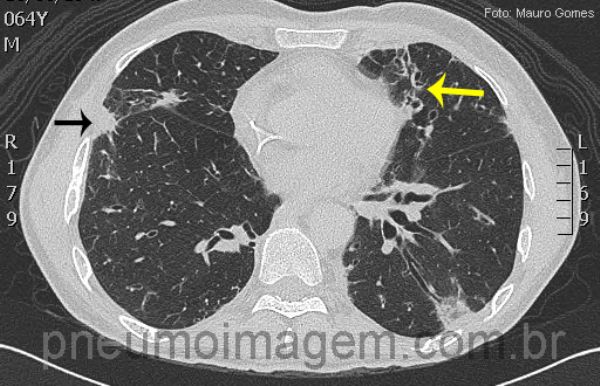

Opacidade com tendência à formação de nódulo (seta preta) e bronquiectasias (seta amarela). Nestes cortes não observamos o sinal do halo, característico de Aspergilose Invasiva.

Nodular opacity (black arrow) and bronchiectasis (yellow arrow). On these images is not seen the halo sign, characteristic of AI.